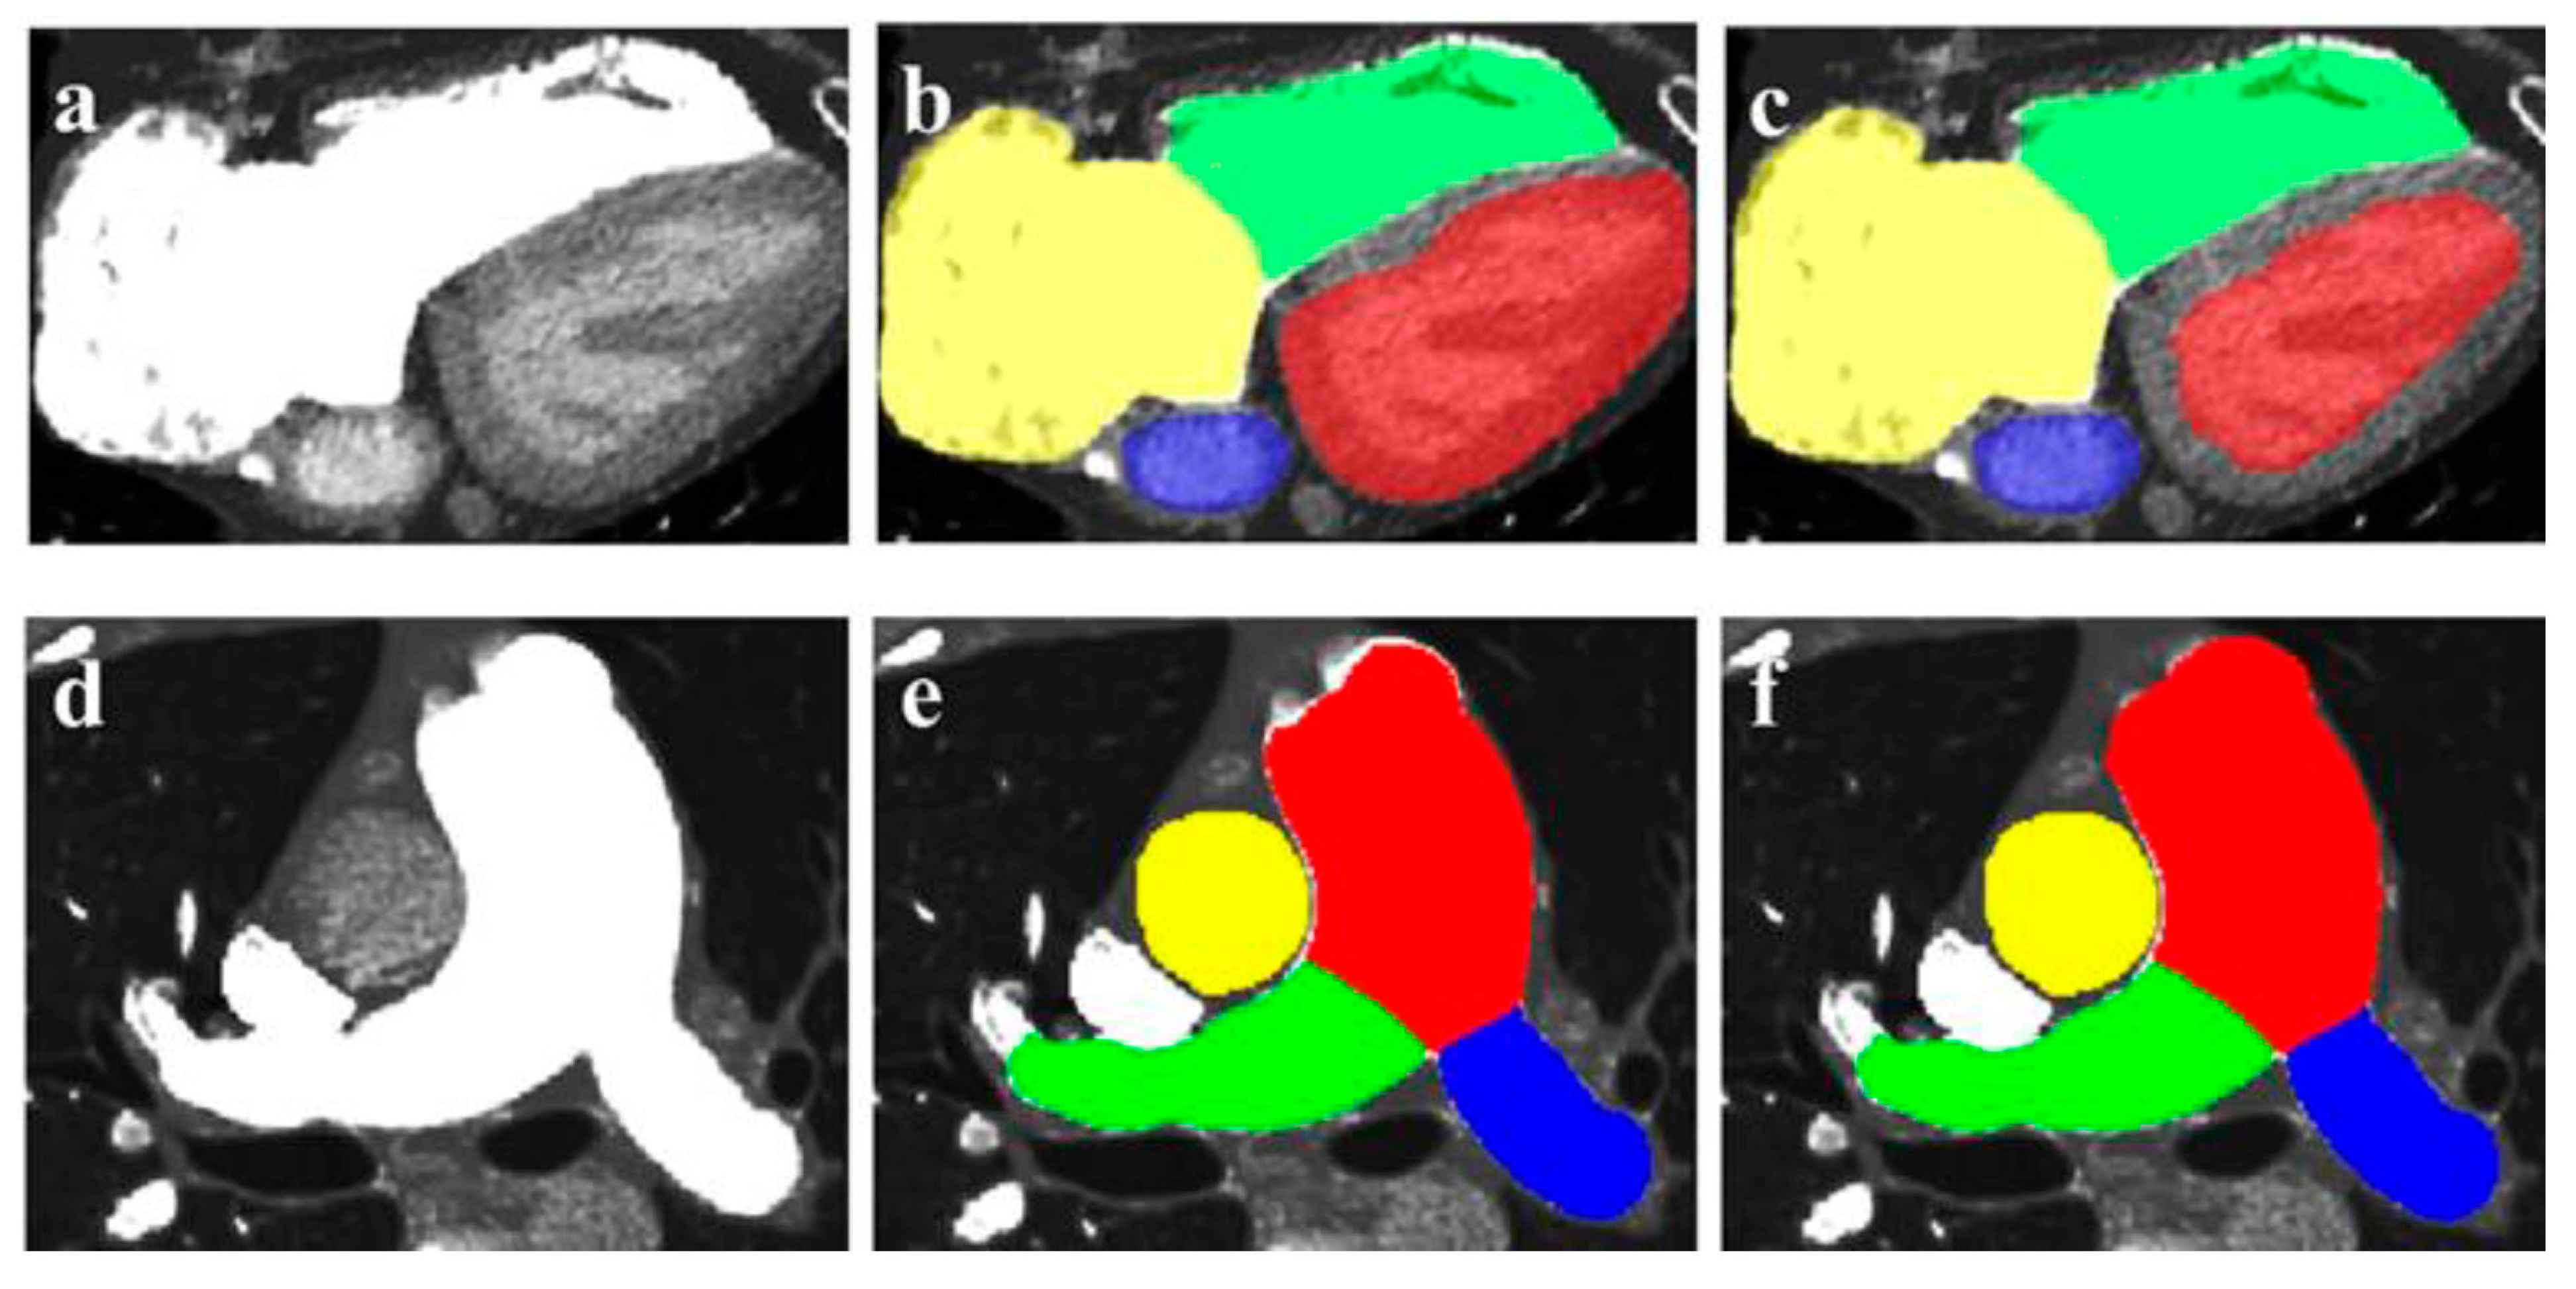

- Zhou, Z.; Gao, Y.; Zhang, W.; Bo, K.; Zhang, N.; Wang, H.; Wang, R.; Du, Z.; Firmin, D.; Yang, G.; et al. Artificial intelligence–based full aortic CT angiography imaging with ultra-low-dose contrast medium: A preliminary study. Eur. Radiol. 2023, 33, 678–689. [Google Scholar] [CrossRef]